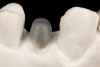

Fig 23. The completed post and core with an ideal ferrule dimension.

Figure 23

Fig 24. Occlusal view of the all-ceramic crown preparation with a full chamfer providing a 2 mm ferrule of sound tooth structure.

Figure 24

The completed post and core displayed an ideal ferrule dimension (Figure 23 and Figure 24). Radiographic review revealed an optimal integration at the adhesive interfaces (Figure 25). A laboratory-processed composite crown completed the optimal integration between the components of the post-retained system and provided structural integrity for intraradicular rehabilitation (Figure 26).